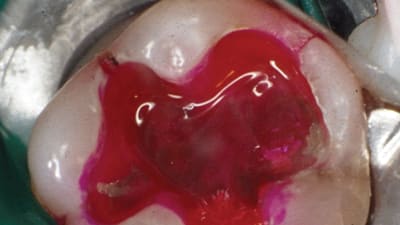

Online Only Periodontics Online Only Preservation of Natural Gingival Pigmentation When Treating Multiple Gingival Recession Defects By Douglas H. Mahn, DDS March 01, 2018 10 min read